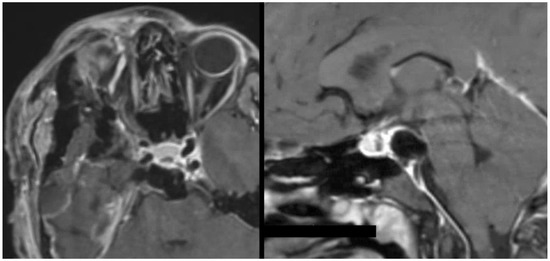

3.5.1. Case 1

3.5.2. Case 2